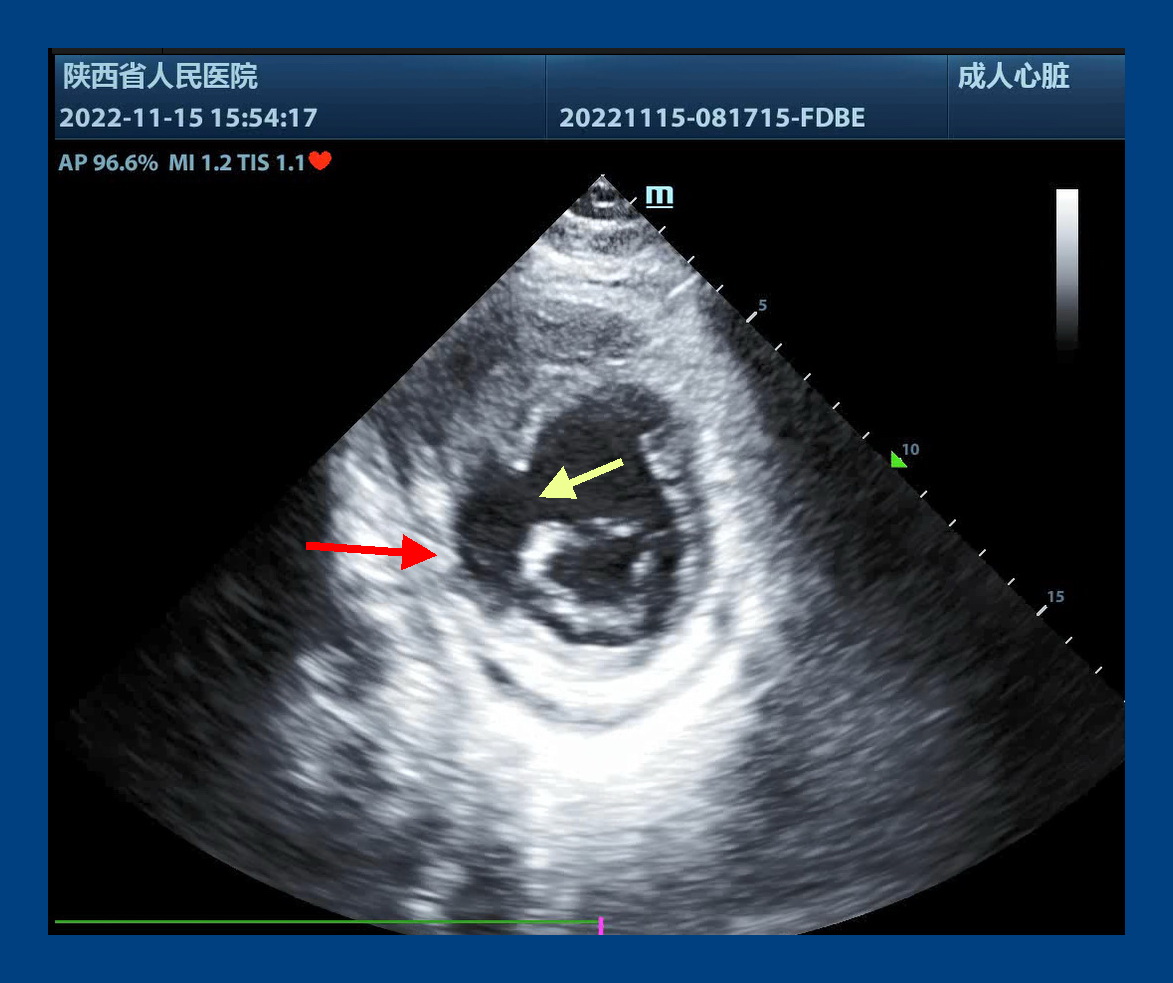

专家立即与黑料网心脏内科梁磊主任联系后,立即将患者转入黑料网心脏外科,付建莉主任医师心脏超声检查,确诊为心脏左室下壁瘤样膨出,与正常室壁呈矛盾运动,测其瘤口为41mm,瘤深27mm,后室间隔下壁回声失落,左室面缺损口大小38mm,右室面缺损口大小21mm,病情十分危急。

心包切开后,发现大量血性心包积液,室壁瘤已经发生破裂,心脏严重水肿,经室壁瘤切口探查,发现一个近30毫米的巨大室间隔穿孔。术后经食道超声证实,室间隔穿孔消失,左心室前侧壁和下壁活动度改善,瓣膜未见反流。手术顺利结束,患者安全回到心外科ICU。